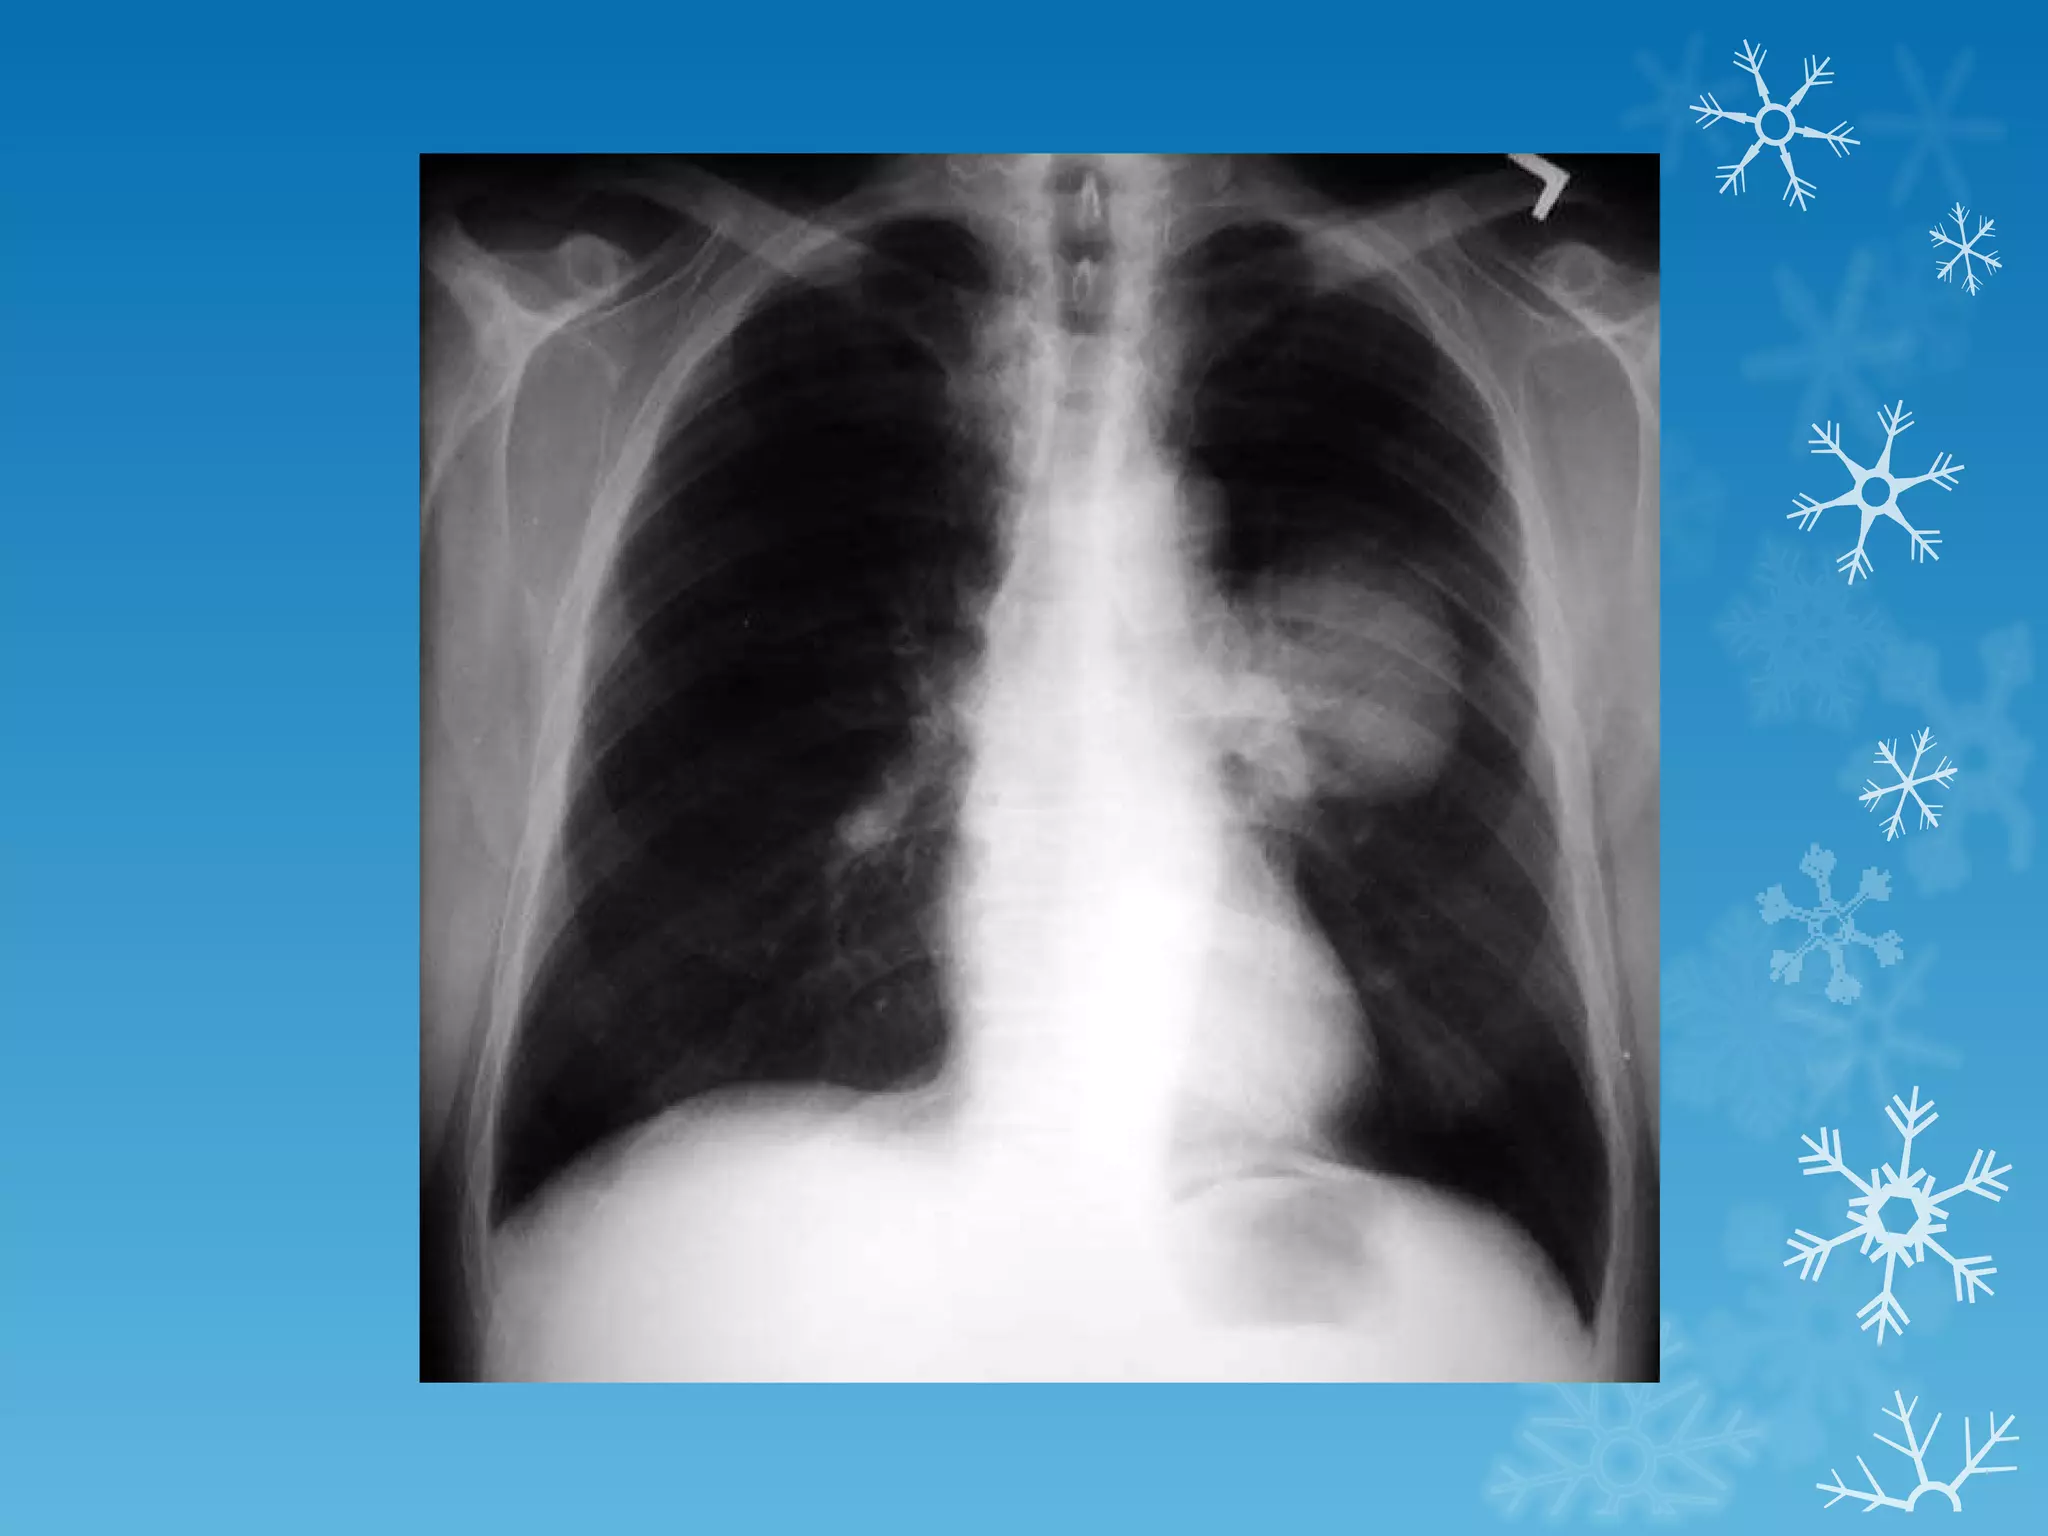

This document discusses chest x-ray interpretation and provides guidance on evaluating x-rays. It explains that tissue density determines how an x-ray beam penetrates, with denser tissues appearing whiter and less dense tissues appearing blacker. It also outlines different chest x-ray views and factors to consider like patient orientation, age, gender, and rotation. Abnormalities are described as appearing too white, too black, too large, or in the wrong place. The document stresses a systematic approach of identifying, localizing, describing lesions, and providing differential diagnoses.